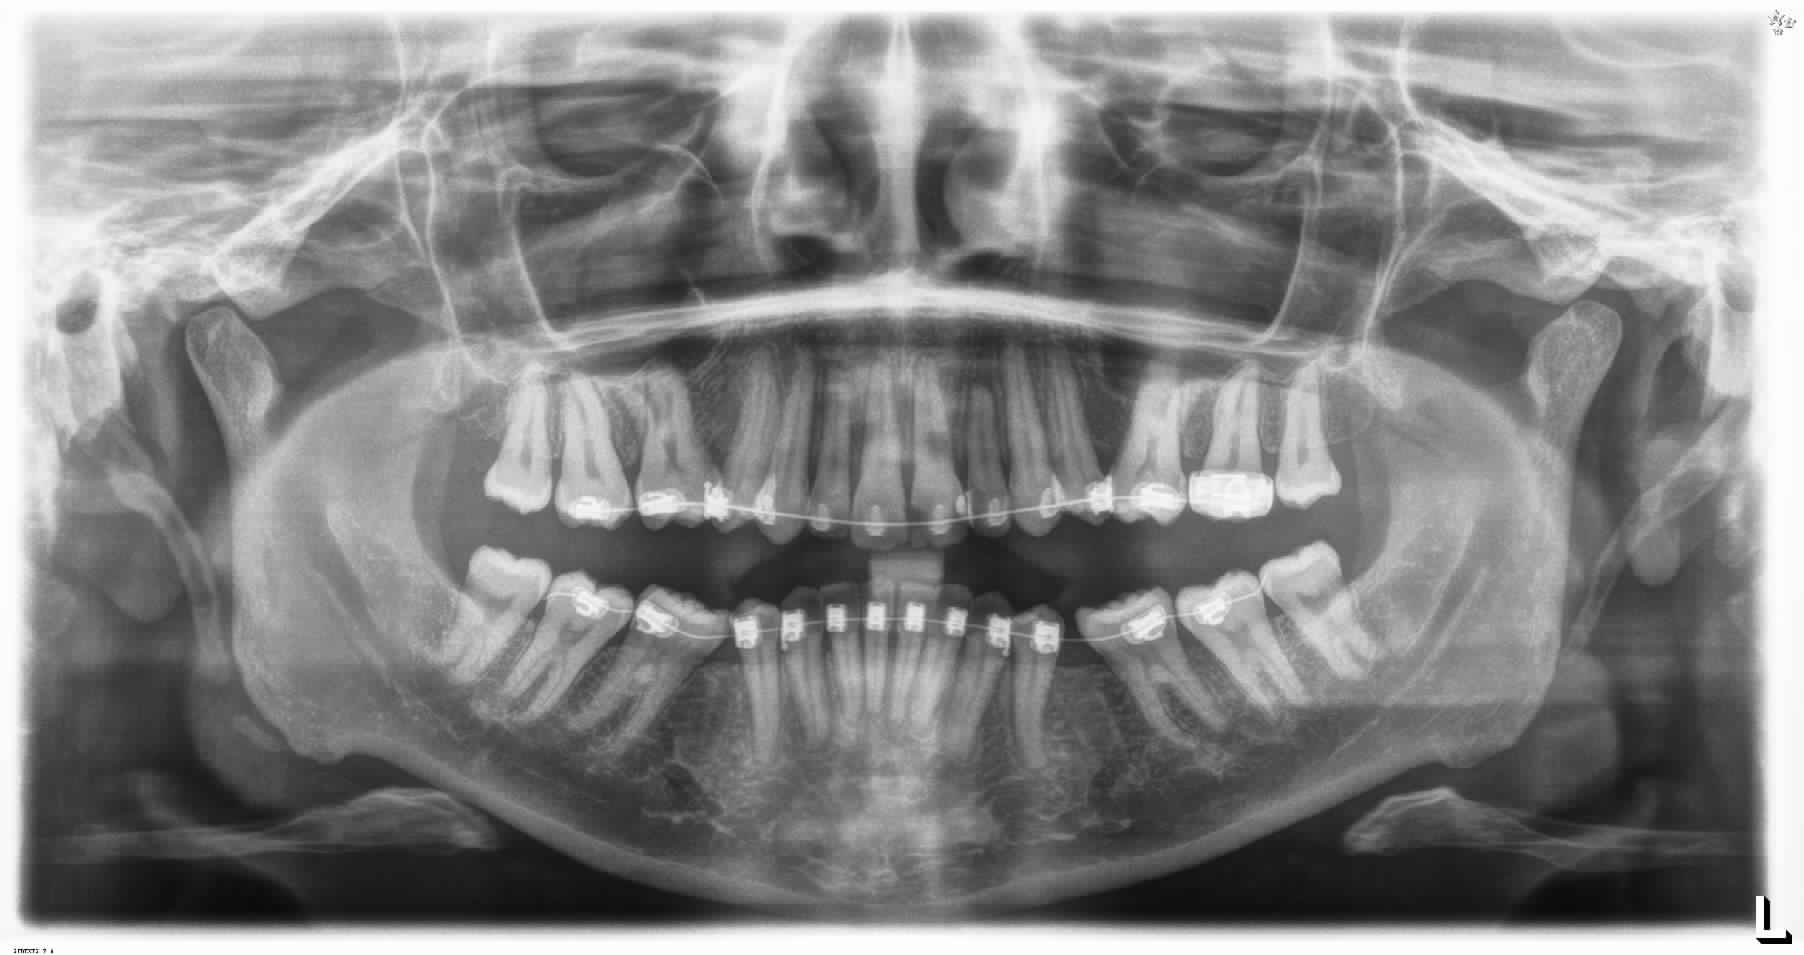

je sollicite vos avis sur ce cas adulte en cours de traitement, avec avulsion des 5 , la supraclusion et la courbe de spee s'est accentuée au cours de la fermeture des espaces , je suis en autoligaturant AO avec des fils actuellement en 14.25 Cuniti ?

Dans votre cas vous avez créer une flexion de l'arcade maxillaire et mandibulaire en essayant de fermer les espaces par chaînette sur un arc qui n'est pas stable (14/25 Cooper niti).

Les extractions dans votre cas (5/5) avaient besoin d'un ancrage maximal au maxillaire ( arc de nance , tip back , toe in , offset)

Et une perte d'ancrage mandibulaire pour aider a la mésialisation des molaires du bas.

Ton problème vient du fait que tu as mis une chainette avec des molaires bien solidarisées (secondes avec premières) au lieu d'un élastique de classe ll qui aurait pu mésialer la 6 et fermer l'espace. Je te rappelle que tu étais en classe ll molaires au départ.

L'arcade maxillaire et mandibulaire ont bien subit une flexion en fermant les espaces des extractions par :

-une chaînette qui a générée des forces anteroposterieures des deux côtés en brisant l'ancrage postérieur.

- un arc qui n'est pas rigide provoquant l'effet bowing.